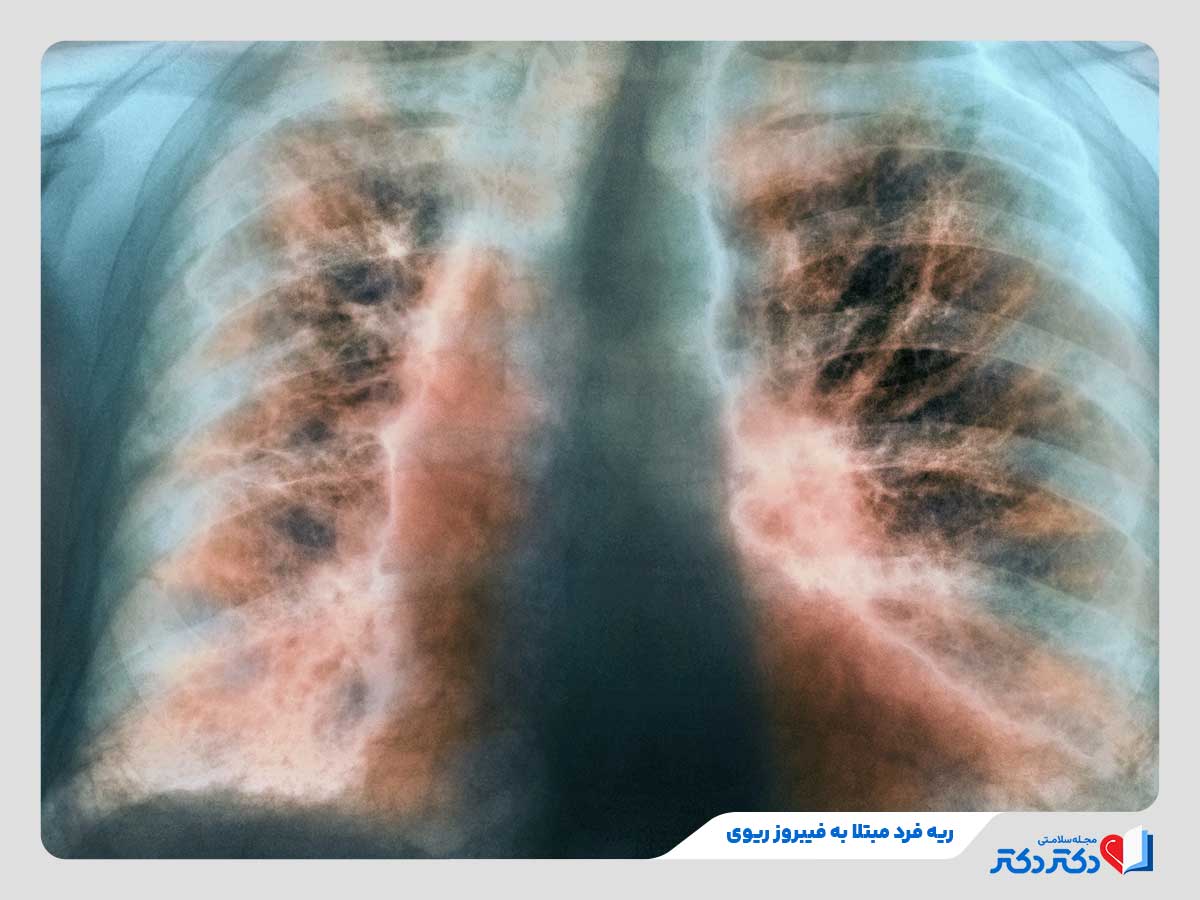

بیماریهای فیبروتیک ریه

این بیماری های ریه شامل حالاتی می باشند که در آنها بافت ریه به مرور زمان دچار فیبروز (راه اندازی بافت اسکار) میبشود. این بافت اسکار سفت و غیرقابل انعطاف است و علتکاهش ظرفیت ریه، سختی تنفس و افت انتقال اکسیژن میبشود. بیماران مبتلا به این بیماری زیاد تر حس میکنند که نمی توانند نفس عمیق بکشند. بیماریهای شایع در این دسته شامل موارد زیر خواهد شد:

- فیبروز ریوی ایدیوپاتیک (IPF) از شایعترین نوع فیبروز ریه با علت ناشناخته

- فیبروز ناشی از روبه رو با مواد شیمیایی یا گرد و غبار همانند پنوموکونیوز، آزبستوز (در تاثییر استنشاق گرد آزبست) و سیلیکوز

- فیبروز ناشی از درمانهای دارویی یا پرتو درمانی

- فیبروز ثانویه به بیماریهای خودایمنی همانند اسکلرودرمی